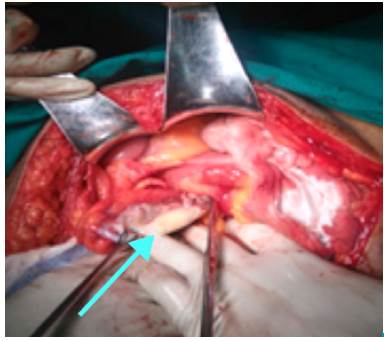

An exploratory laparotomy was decided with conventional appendectomy plus raffia with appendicular base, similar to the Parker-Kerr technique. Findings included appendiceal tumors with a wide base of thick walls and mucoid content. The samples taken were sent to pathology (Figure 2).

Sample of dilated cecal appendix compatible with mucocele.

Figure 2: Sample of dilated cecal appendix compatible with mucocele.

Source: Own elaboration based on the data obtained in the study.

Since the condition of the patient resembled an acute abdomen of 5 days of evolution, an exploratory laparotomy was performed, in which a dilated tumor-like appendix was found, as well as necrosis in its lower third and broad base, which led to suspect mucocele. The caecum was in good condition, so a conventional appendectomy was performed.